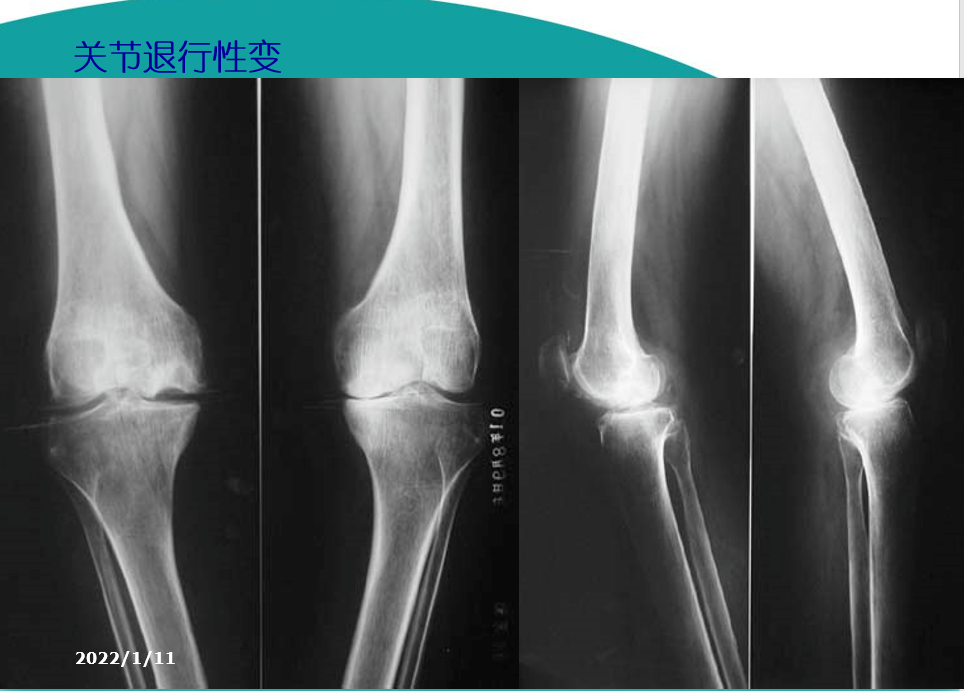

X线检查基本特征1.关节间隙变窄:成人膝关节间隙为4mm,小于3mm即为关节间隙狭窄,60岁以上的老人膝关节间隙为3mm,小于2mm为关节间隙狭窄。2.软骨下骨板硬化:软骨下骨板致密、硬化,负重软骨下骨质内可见囊性改变。3.骨赘形成